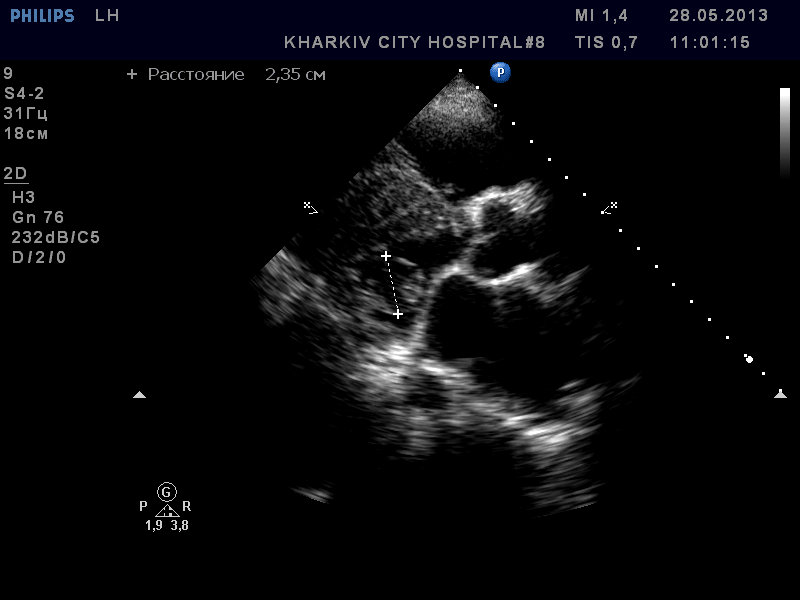

Пациентка 83 лет. Жалобы на сильную одышку в теч. последнего месяца.

В полости левого желудочка в базальном сегменте имеется образование с неровным контуром до 2.4см- вероятно миксома левого желудочка.

кальциноз створок АК, дилатация левого предсердия, правых полостей, выраженная недостаточность ТК и клапана ЛА, гипертрофия левого желудочка. Дополнительные косые хорды левого желудочка. Высокая ЛГ (АТ/ЕТ- 0.20 Рсред. ЛА-69мм рт.ст.).

п.с. Инсультов в анамнезе нет